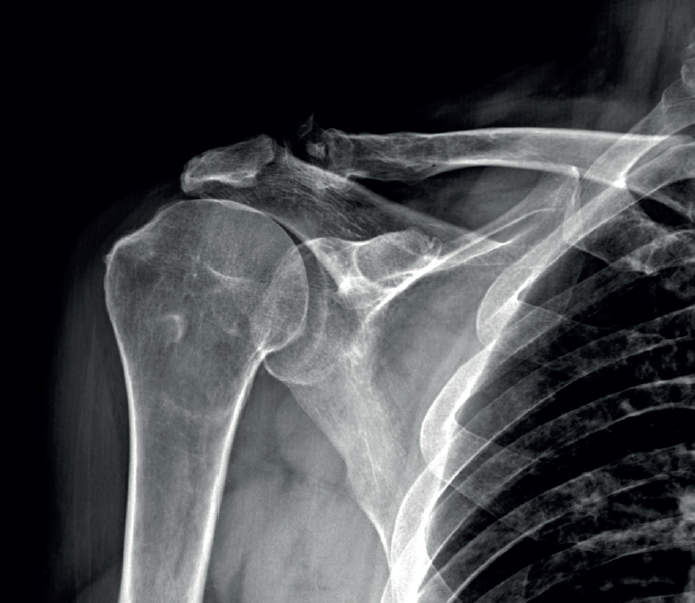

The preoperative evaluation must take a number of aspects into account, including patient age, pain, disability, functional demands and the patient expectations. In this respect, the patient must be duly informed about the expectable functional results. We also must consider other factors that can affect the surgical outcomes, such as patient comorbidities, deltoid muscle and subscapularis function, the integrity of the coracoacromial arch, the presence of arthrotic changes (Figure 1), and the need for the patient to enter prolonged rehabilitation. The main symptoms of massive ruptures of the rotator cuff are typically pain, weakness and loss of mobility(13,14). Irreparable massive ruptures are a common cause of intense pain and often prove extremely disabling for the patient. In general, patients with posterosuperior cuff rupture present reduced flexion-elevation and abduction, and total or partial loss of active external rotation(15,16). A positive external-rotation lag sign and positive hornblower sign are indicative of a deficit of the posterior cuff with the disabling of external rotation, and are associated with irreparable rupture of the teres minor and advanced fatty infiltration(17,18). The appearance of these signs at exploration is associated with poor outcomes of transfer of the latissimus dorsi(13,19). Weakness proves highly variable, and in extreme degrees we observe pseudo-paralysis. Although consensus is lacking, pseudo-paralysis in elevation could be defined as the inability to perform active flexion-elevation of 90º in the absence of nerve damage and with preserved passive mobility. External rotation pseudo-paralysis is defined as the complete loss of active external rotation strength in the presence of unrestricted passive external rotation and the absence of neurological lesions. Some authors consider pseudo-paralysis to be a contraindication to transfer of the latissimus dorsi(20), and is seen to be associated with poor outcomes, since it does not afford the necessary strength to overcome a pseudo-paralytic shoulder and achieve postsurgical elevation(12). Most authors agree that the deltoid muscle must be in good condition in order to perform transfer(21). Irreparable rupture of the subscapularis is an absolute contraindication to this kind of transfer, due to anterior escape of the humeral head when the deltoid muscle contracts in the absence of the subscapularis(9). However, good results can be obtained in partial ruptures of the upper third of the subscapularis that can repaired in the same surgical step(21)(Figures 2 and 3).

The presence of severe osteoarthrosis, above Hamada stage 2(22), or the existence of anterosuperior escape, is considered to be a contraindication to transfer, since both are associated with poor outcomes in transfer of the latissimus dorsi(23,24).